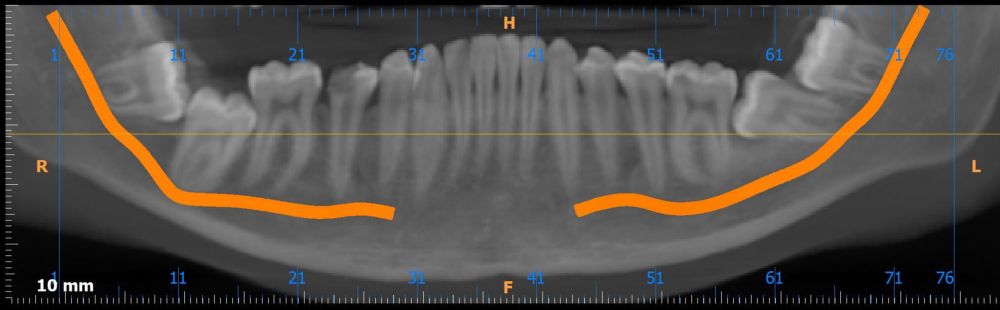

Métodos: Se presenta el caso clínico de un paciente varón de 18 años en el que, tras la realización de una CBCT de la arcada mandibular, se observó la retención de los segundos molares mandibulares permanentes junto con los terceros molares mandibulares.

Methods: We present the case of an 18-year-old male patient in whom, after performing a CBCT of the mandibular arch, retention of the permanent mandibular second molars was observed, along with the mandibular third molars.